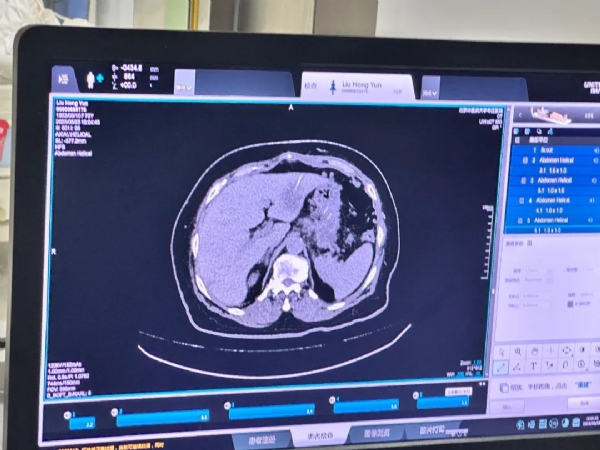

患者为73岁女性,腹部CT检查提示胰占位性病变并疑似肝转移瘤。依据《NCCN指南》推荐,针对疑似转移性胰腺癌患者,优先选择安全性高且诊断明确的穿刺部位(如肝脏转移灶)进行活检。

经肿瘤科医疗团队全面评估患者病情,严格排除手术风险及禁忌证后,在CT室的精准引导下实施经皮肝脏穿刺活检术。此次手术面临多重挑战:术前需综合评估患者基础状况与耐受能力,术中必须精准规划穿刺路径。为最大程度降低风险,手术团队精心设计了经正常肝实质的最大化路径方案,充分利用正常肝组织弹性回缩特性闭合针道,有效减少针道转移及术后出血风险。